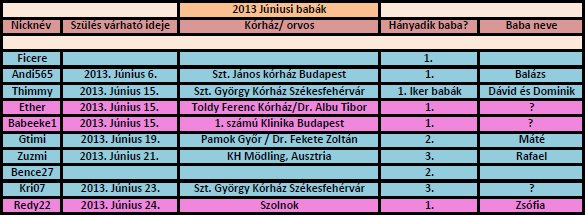

Kecskeméten voltunk 4D-n a fecske gyógycentrumba, és azért mentünk pont oda, mert csupa jót hallottam, meg olvastam róluk. Pont azt kaptam, amit vártam.

Szerintem sem kell aggódnod a két baba közötti súlykülönbségen. Annyira minimális az etérés, lehet, hogy a kövi uh-n már ennyi se lesz. A koruknak teljesen megfelel a súlyuk egyenként!!! Szép fejlettek mindketten.

Íme a képek a babócámról:

Bogyó

Bogyó